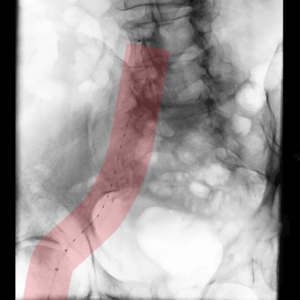

Behandlung des undichten Stentes in der Hauptschlagader:

Nach der Versorgung einer Erweiterung der Hauptschlagader des Bauches kann es zu Undichtheiten des Stentes oder zu einem Zufluss aus kleinen Arterien kommen, die zu einer gefährlichen Zunahme der Erweiterung führen können. Für die Behandlung stehen uns alle Behandlungsmethoden zum Verschließen zur Verfügung.